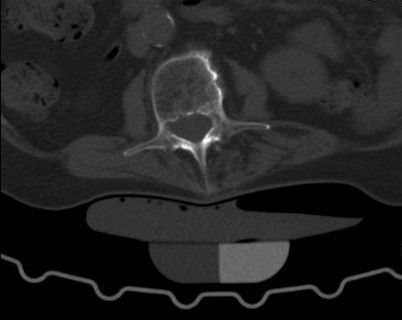

Computertomographie (CT)

Die Computertomographie (kurz CT) ist ein modernes bildgebendes Verfahren mit Röntgenstrahlung, welches erlaubt in kürzester Zeit große Körperabschnitte zu untersuchen. Eine Röntgenröhre umkreist dabei den Patienten und sendet ein dünnes Strahlbündel aus. Das Ergebnis liefert überlagerungsfreie Querschnittsbilder der untersuchten Körperregion, die sich in allen Raumebenen rekonstruieren lassen.

CT-gesteuerte Schmerztherapie

(Periradikuläre Therapie und Facetteninfiltration)

Die Periradikuläre Therapie (PRT) und Facetteninfiltration ist eine bildgesteuerte Schmerztherapie. Diese CT-gesteuerte Infiltration ermöglicht eine sehr gezielte und schonende Behandlung von Rückenschmerzen und in die Arme und Beine ausstrahlenden Schmerzen direkt am Entstehungsort - sie kann also eine sinnvolle Alternative zu operativen Eingriffen darstellen.